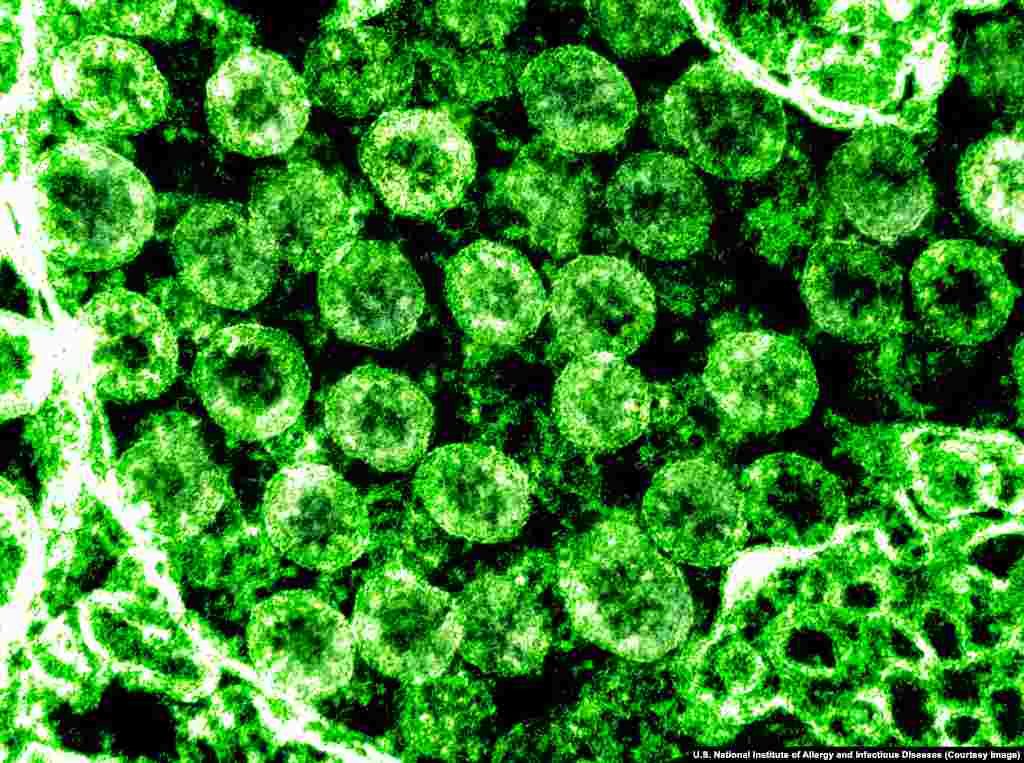

6

Скопление вирионов SARS-CoV-2, которое видно через электронный микроскоп.

Вирионы коронавируса с помощью шипов на своей поверхности прикрепляются к рецепторам в некоторых клетках человеческого организма – особенно в легких – и проникают затем внутрь клетки.

Вирионы коронавируса с помощью шипов на своей поверхности прикрепляются к рецепторам в некоторых клетках человеческого организма – особенно в легких – и проникают затем внутрь клетки.